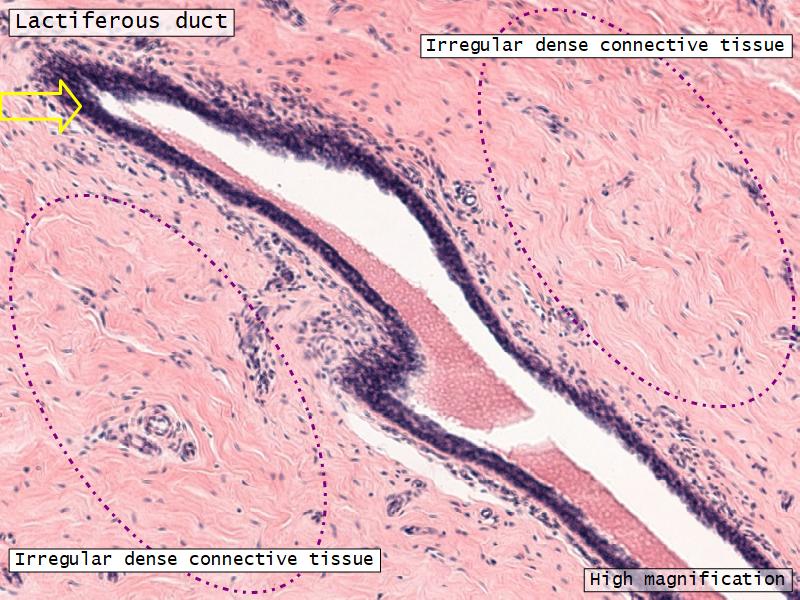

- Lactiferous ducts

- Stratified cuboidal

- Myoepithelial cells

- Underlie lactiferous ducts in most areas

- Basal lamina

- Separate epithelial components from stroma

Morphology

What are the main morphological features of the nipple?

(4)

Morphology

- Covered with skin

- Consists of dense collagenous connective tissue

- Interlaced with smooth muscle fibres

- Contains openings of lactiferous ducts

Skin

- Keratinized stratified squamous epithelium

- Sebaceous glands

Stroma

- Collagenous connective tissue

- Irregular dense connective tissue

- Smooth muscle

- Fibres and bundles

- Lactiferous sinusses

- Stratified cuboidal epithelium